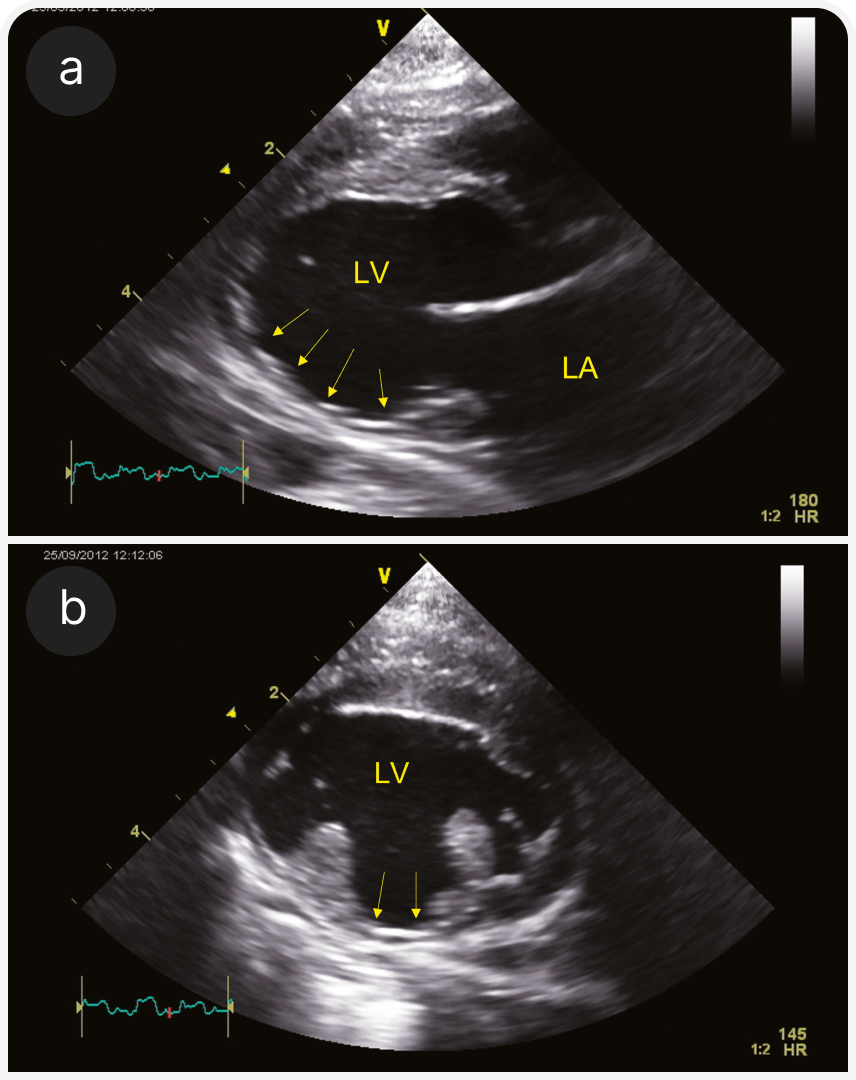

1. Терминальная стадия гипертрофической кардиомиопатии. На сегодняшний день ГКМП — наиболее распространенный тип кардиомиопатии, но на конечных стадиях она может проявляться другими фенотипами. Этот термин используют, если ГКМП отмечена в анамнезе, даже если при обследовании не выявлена сегментарная или генерализованная гипертрофия левого желудочка или выявлена очень легкая гипертрофия. Левый желудочек может быть гипокинетичным или расширенным (Рисунок 2), может быть виден инфаркт миокарда (Рисунок 3).

(b) Проекция RPS по короткой оси на уровне папиллярных мышц; видны предполагаемый инфаркт миокарда и фиброзное замещение у той же кошки, что и на (3a). Видна тонкая стенка ЛЖ (стрелки) между двумя папиллярными мышцами.